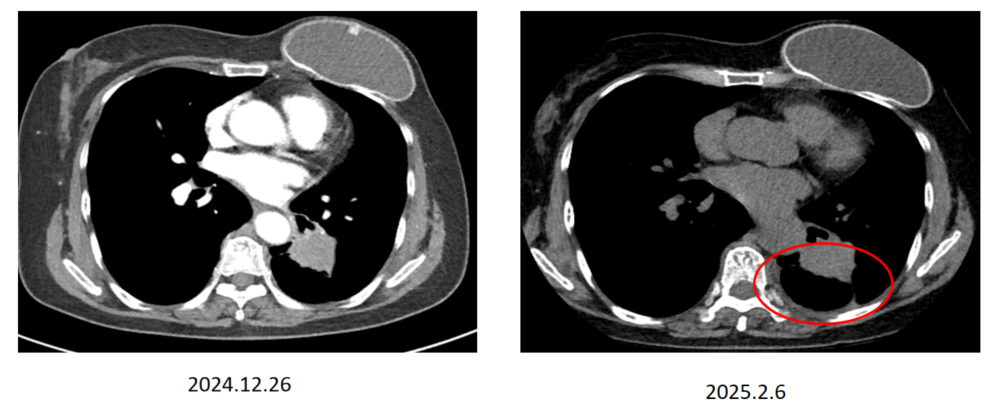

胸部CT( 2024年12月26日):左下叶肿块,多学科会诊(MDT)初步评估倾向于早期肺癌,但患者的手术被推迟了六个多星期。

手术治疗( 2025年2月7日):患者接受电视辅助胸腔镜(VATS)探查术。术中意外发现胸膜种植,遂终止根治性手术并关闭胸腔。

疗效评价:胸部CT显示治疗4个月后肺部病灶有所缩小,达到疾病稳定(SD)状态。在将埃万妥单抗IV转换为SC后,左肺下叶的肿瘤病灶持续缩小,截至目前SD超过9个月。